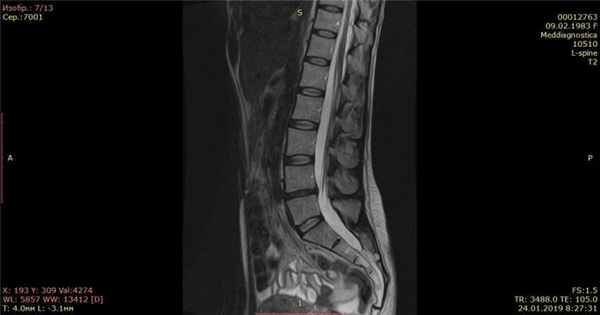

Осмотрели Ирину неврологически и ортопедически, исследовали позвоночник на МРТ и рентгене. Оказалось, что у нее очень большая левосторонняя грыжа размером 12 мм.

На МРТ показано излечение грыжи диска (до- и после лечения).

Контрольный МРТ, через 5 месяцев показал полное отсутствие грыжи диска (см. снимки Ирины ниже):

Обратите внимание на даты проведения МРТ в правом нижнем углу. МРТ исследования проведены на одном аппарате 1.5 теслы в клинике «Меддиагностика» в процессе лечения Ирины. МРТ позвоночника позволяет отследить динамику уменьшения грыжи диска.